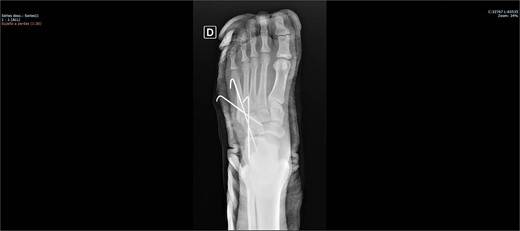

On physical examination, there was pain upon palpation over the dorso-lateral region of the midfoot, mild edema, hyperemia, inability to walk, and restricted ankle extension. Based on the physical examination, radiographs were requested. The examinations (Figs 1 and 2) showed inferomedial displacement of the cuboid bone without the presence of a fracture, diagnosing an isolated cuboid dislocation. He was immobilized and admitted for an open surgical reduction procedure.

The patient was placed on the surgical table in the supine position, anesthetized with spinal anesthesia, and given prophylactic antibiotic therapy with 2 g of cefazolin. After exsanguination of the lower limb, a dorsolateral incision was made on the foot over the cuboid bone and deepened through the layers until complete visualization of the cuboid bone was achieved. There was an interposition of ligamentous structures, such as the calcaneocuboid ligament, dorsal cuneocuboid ligament, and dorsal tarsometatarsal ligaments. After removing all structures that were interposed and preventing reduction, the cuboid was reduced easily, but instability was observed. Due to the instability found, percutaneous fixation was performed with three Kirschner wires: the first extending from the fourth metatarsal to the calcaneus, traversing the cuboid; the second from the fifth metatarsal to the cuboid; and the third from the cuboid to the calcaneus, from anterior-dorsal to posterior-plantar (Figs 3 and 4). After complete fixation, the stability of the cuboid was observed, maintaining it in the correct position, confirmed with fluoroscopy during surgery.